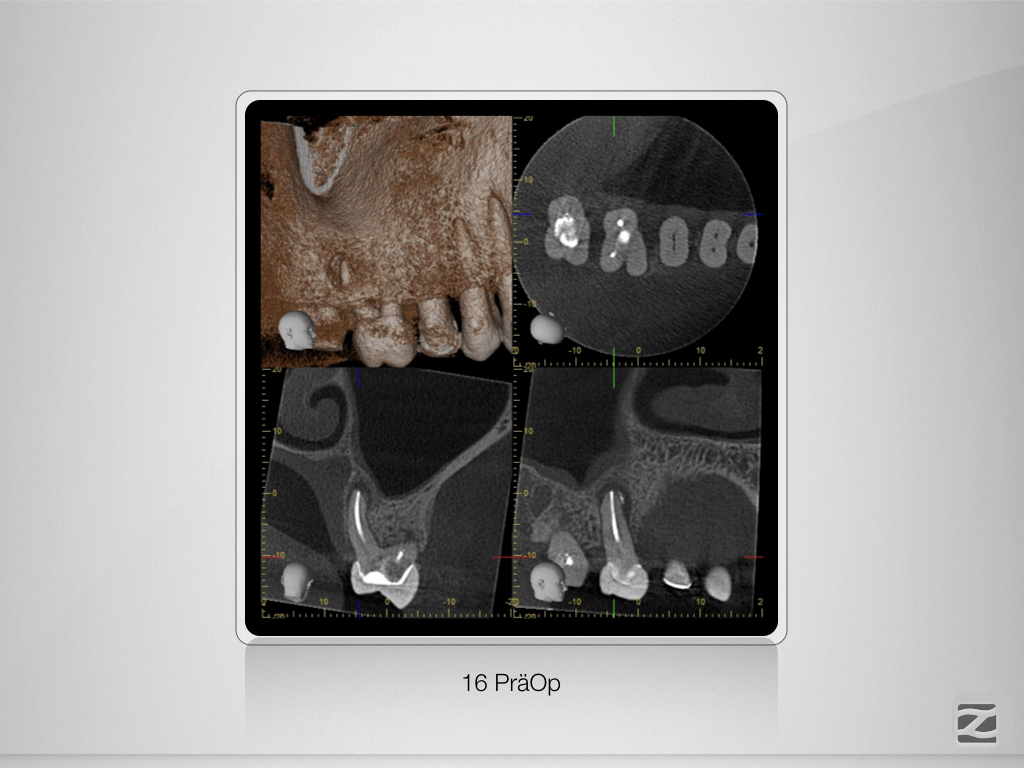

Wie hältst Du es mit dem Haarriss?